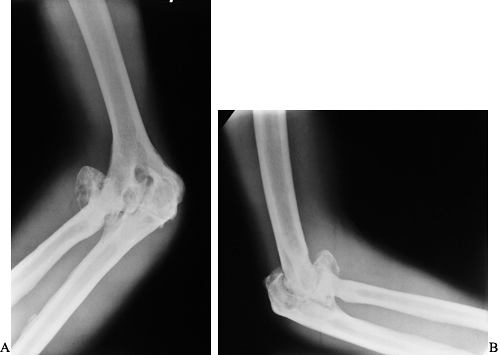

Figure 136.6. AP (A) and lateral (B)

radiographs showing end-stage arthropathy with large synovial cysts, complete loss of cartilage interval, flattening of the opposing joint surfaces, ossification of the posterior capsule, and nearly complete fibrous ankylosis. |